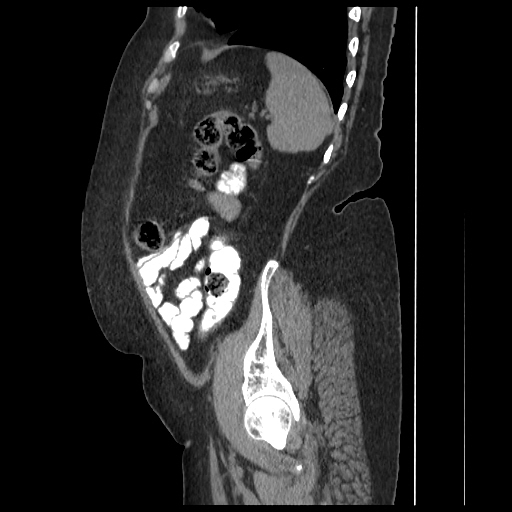

A 70 years old woman with Obstractive jaundice & palpable GB